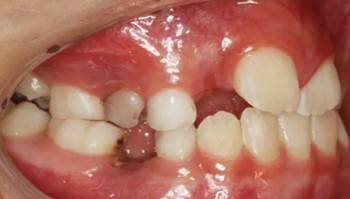

1、 患者 男 7歲 右下乳IV因齲早失

3、曲面斷層片 示恒牙萌出間隙不足